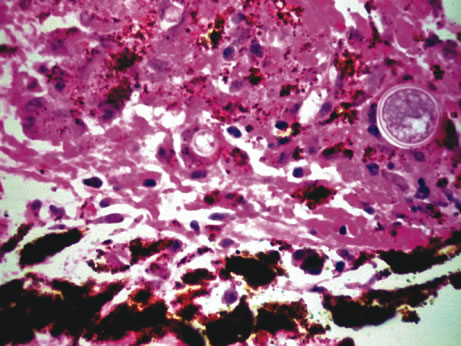

Inflammatory conditions may also lead to iris nodules. Patients suffering from fungal endophthalmitis may demonstrate an irregular yellow-white mass on the iris. Histologically, these appear as necrotizing granulomas containing mycotic agents (Fig. 2). In juvenile xanthogranuloma, a yellowish-gray iris lesion may be associated with spontaneous hyphema, and histopathologically the nodules demonstrate diffuse histiocytic infiltrate (Fig. 3). Multinucleated giant cells displaying peripheral foamy cytoplasm are also noted; these cells are known as Touton giant cells.29 The giant cells and the histiocytes contain lipid that can be demonstrated by oil red O stain.

Fig. 2. Coccidioidomycosis. Iris stroma shows necrotizing granuloma containing mycotic organisms. The organisms show features of Coccidioides immitis. (Hemotoxylin-eosin ×60.)